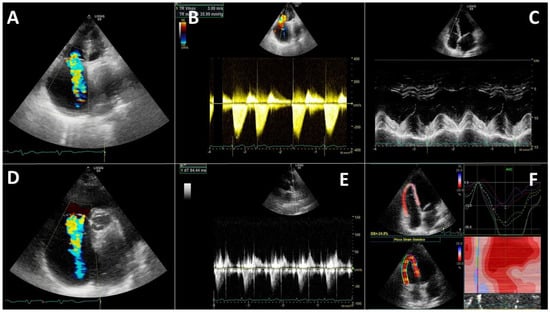

- Szekely, Y.; Lichter, Y.; Taieb, P.; Banai, A.; Hochstadt, A.; Merdler, I.; Gal Oz, A.; Rothschild, E.; Baruch, G.; Peri, Y.; et al. Spectrum of Cardiac Manifestations in COVID-19: A Systematic Echocardiographic Study. Circulation 2020, 142, 342–353. [Google Scholar] [CrossRef]

- Dweck, M.R.; Bularga, A.; Hahn, R.T.; Bing, R.; Lee, K.K.; Chapman, A.R.; White, A.; Di Salvo, G.; Sade, L.E.; Pearce, K.; et al. Global evaluation of echocardiography in patients with COVID-19. Eur. Heart J. Cardiovasc. Imaging 2020, 21, 949–958. [Google Scholar] [CrossRef]

- Barman, H.A.; Atici, A.; Tekin, E.A.; Baycan, O.F.; Alici, G.; Meric, B.K.; Sit, O.; Genc, O.; Er, F.; Gungor, B.; et al. Echocardiographic features of patients with COVID-19 infection: A cross-sectional study. Int. J. Cardiovasc. Imaging 2021, 37, 825–834. [Google Scholar] [CrossRef]

- Li, Y.; Li, H.; Zhu, S.; Xie, Y.; Wang, B.; He, L.; Zhang, D.; Zhang, Y.; Yuan, H.; Wu, C.; et al. Prognostic Value of Right Ventricular Longitudinal Strain in Patients With COVID-19. JACC Cardiovasc. Imaging 2020, 13, 2287–2299. [Google Scholar] [CrossRef] [PubMed]

- Lazzeri, C.; Bonizzoli, M.; Batacchi, S.; Peris, A. Echocardiographic assessment of the right ventricle in COVID -related acute respiratory syndrome. Intern. Emerg. Med. 2021, 16, 1–5. [Google Scholar] [CrossRef] [PubMed]

- D’Alto, M.; Marra, A.M.; Severino, S.; Salzano, A.; Romeo, E.; De Rosa, R.; Stagnaro, F.M.; Pagnano, G.; Verde, R.; Murino, P.; et al. Right ventricular-arterial uncoupling independently predicts survival in COVID-19 ARDS. Crit. Care 2020, 24, 670. [Google Scholar] [CrossRef]

- Xie, Y.; Wang, L.; Li, M.; Li, H.; Zhu, S.; Wang, B.; He, L.; Zhang, D.; Zhang, Y.; Yuan, H.; et al. Biventricular Longitudinal Strain Predict Mortality in COVID-19 Patients. Front. Cardiovasc. Med. 2021, 7, 418. [Google Scholar] [CrossRef]

- Ozer, P.K.; Govdeli, E.A.; Baykiz, D.; Karaayvaz, E.B.; Medetalibeyoglu, A.; Catma, Y.; Elitok, A.; Cagatay, A.; Umman, B.; Oncul, A.; et al. Impairment of right ventricular longitudinal strain associated with severity of pneumonia in patients recovered from COVID-19. Int. J. Cardiovasc. Imaging 2021. [Google Scholar] [CrossRef] [PubMed]

- Gibson, L.E.; Di Fenza, R.; Lang, M.; Capriles, M.I.; Li, M.D.; Kalpathy-Cramer, J.; Little, B.P.; Arora, P.; Mueller, A.L.; Ichinose, F.; et al. Right Ventricular Strain Is Common in Intubated COVID-19 Patients and Does Not Reflect Severity of Respiratory Illness. J. Intensive Care Med. 2021, 36, 900–909. [Google Scholar] [CrossRef]

- Wibowo, A.; Pranata, R.; Astuti, A.; Tiksnadi, B.B.; Martanto, E.; Martha, J.W.; Purnomowati, A.; Akbar, M.R. Left and right ventricular longitudinal strains are associated with poor outcome in COVID-19: A systematic review and meta-analysis. J. Intensive Care 2021, 9, 9. [Google Scholar] [CrossRef]